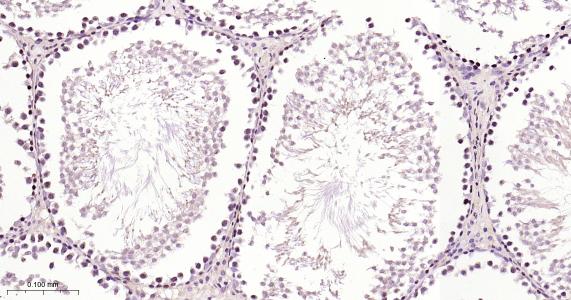

Paraformaldehyde-fixed, paraffin embedded Human Testicles; Antigen retrieval by boiling in sodium citrate buffer (pH6.0) for 15 min; Antibody incubation with TXNRD1 Monoclonal Antibody, Unconjugated(bsm-61558R) at 1:200 overnight at 4°C, followed by conjugation to the bs-0295G-HRP and DAB (C-0010) staining.

Paraformaldehyde-fixed, paraffin embedded Rat Testicles; Antigen retrieval by boiling in sodium citrate buffer (pH6.0) for 15 min; Antibody incubation with TXNRD1 Monoclonal Antibody, Unconjugated(bsm-61558R) at 1:200 overnight at 4°C, followed by conjugation to the bs-0295G-HRP and DAB (C-0010) staining.

Paraformaldehyde-fixed, paraffin embedded Mouse Testicles; Antigen retrieval by boiling in sodium citrate buffer (pH6.0) for 15 min; Antibody incubation with TXNRD1 Monoclonal Antibody, Unconjugated(bsm-61558R) at 1:200 overnight at 4°C, followed by conjugation to the bs-0295G-HRP and DAB (C-0010) staining.